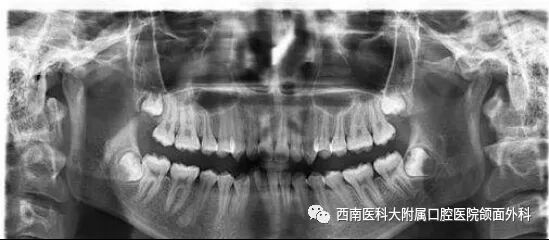

何芸表示,通过对患者血常规、血糖和凝血四项等查血项目检查可以检查患者的身体状况,比如目前有没有感染,凝血功能有没有障碍等,以判断是否进行手术,手术前是否要准备预防性用药等急救措施。牙片是牙科常见的X线片的统称。X线检查是目前应用最普遍的辅助检查手段,用于龋齿、牙髓炎、根尖周病、牙周病、口腔颌面部感染、外伤、先天发育异常、良恶性肿瘤等疾病的辅助检查。通过拍牙片可以对病人所患牙齿疾病的诊断、判断提供更为精准的医疗服务。据了解,西南医科大学附属口腔医院口腔颌面外科门诊开展微创拔牙、心电监护拔牙、口腔颌面部门诊手术等治疗。现有医护人员20余名,其中教授1名、副教授3名,博士4名、硕士7名;留学归国人员4名。拥有SAT计算机控制无痛麻醉仪,法国赛特力Piezotome超声骨刀,心电监护仪等先进医疗设备。